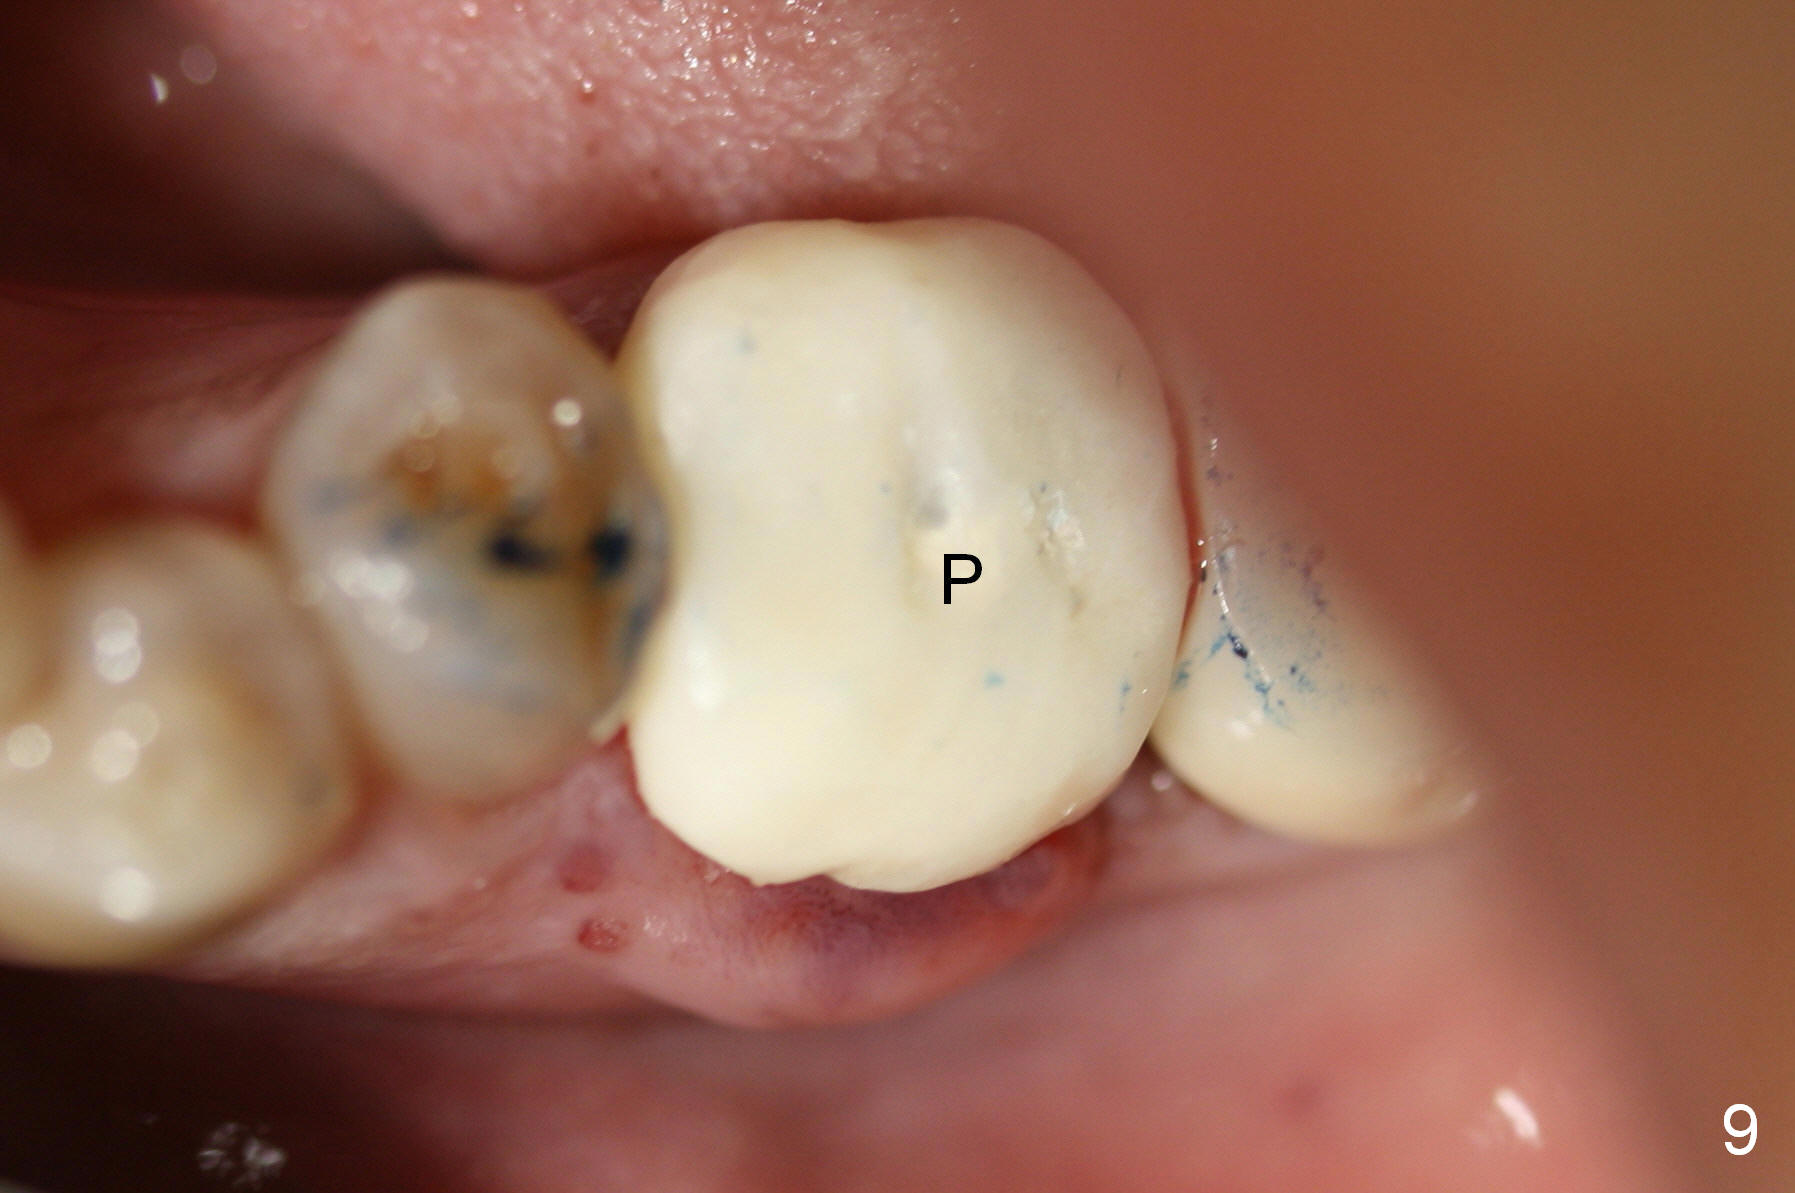

A 47-year-old lady lives out of town and presents to clinic with chief complaint "lower left back tooth easily bleeding with food impaction". Dental history and examination reveals failure of endo retreat of the tooth #19 (Fig.1), buccal gingival swelling (S), open access (A) and furcal and mesial periapical radiolucency (Fig.2 *). She is pleased to know availability of immediate implant and immediate provisional and accepts and receives the treatment at the same visit. The immediate implant (tissue-level) is designed to be as large as 7 mm and as long as 17 mm (Fig.3). To reduce paresthesia (yellow dashed line: the possible upper border of the Inferior Alveolar Canal)), a shorter implant (14 mm long in red line) is preferred. The tooth is extracted with sectioning. Granulation tissue is removed from the furca. The buccal plate appears to be intact. The septum is flat (Fig.4,10a S). Osteotomy starts in the middle of the septum with a 1.2 mm drill (Fig.10b red circle). As osteotomy increases in diameter (Fig.5 O), the apical end appears to be deviated mesiobuccally (Fig.10c large red circle). When a 6x17 mm tapered tap is being placed 14 mm deep (Fig.6 T), vibration of the buccal plate is seemingly felt at the apex (Fig.10d green circle). Further osteotomy may perforate the buccal plate. A 6x14 mm tissue-level implant is placed with >60 Ncm of insertion torque (Fig.7,8 I), followed by a 5x3 mm abutment (A) and bone graft (* in the remaining socket gap). An immediate provisional is cemented without occlusal contact (Fig.9 P).